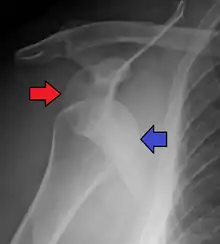

Lightbulb sign indicative of posterior shoulder dislocation shown on the left. On the right, the same shoulder after reduction.

Posterior dislocations are uncommon, and are typically due to the muscle contraction from electric shock or seizure.[5] They may be caused by strength imbalance of the rotator cuff muscles. People with dislocated shoulders typically present holding their arm internally rotated and adducted, and exhibiting flattening of the anterior shoulder with a prominent coracoid process.

Posterior dislocations may go unrecognized, especially in an elderly person[11] and in people who are in the state of unconscious trauma.[12] An average interval of 1 year was noted between injury and diagnosis in a series of 40 people.[13]